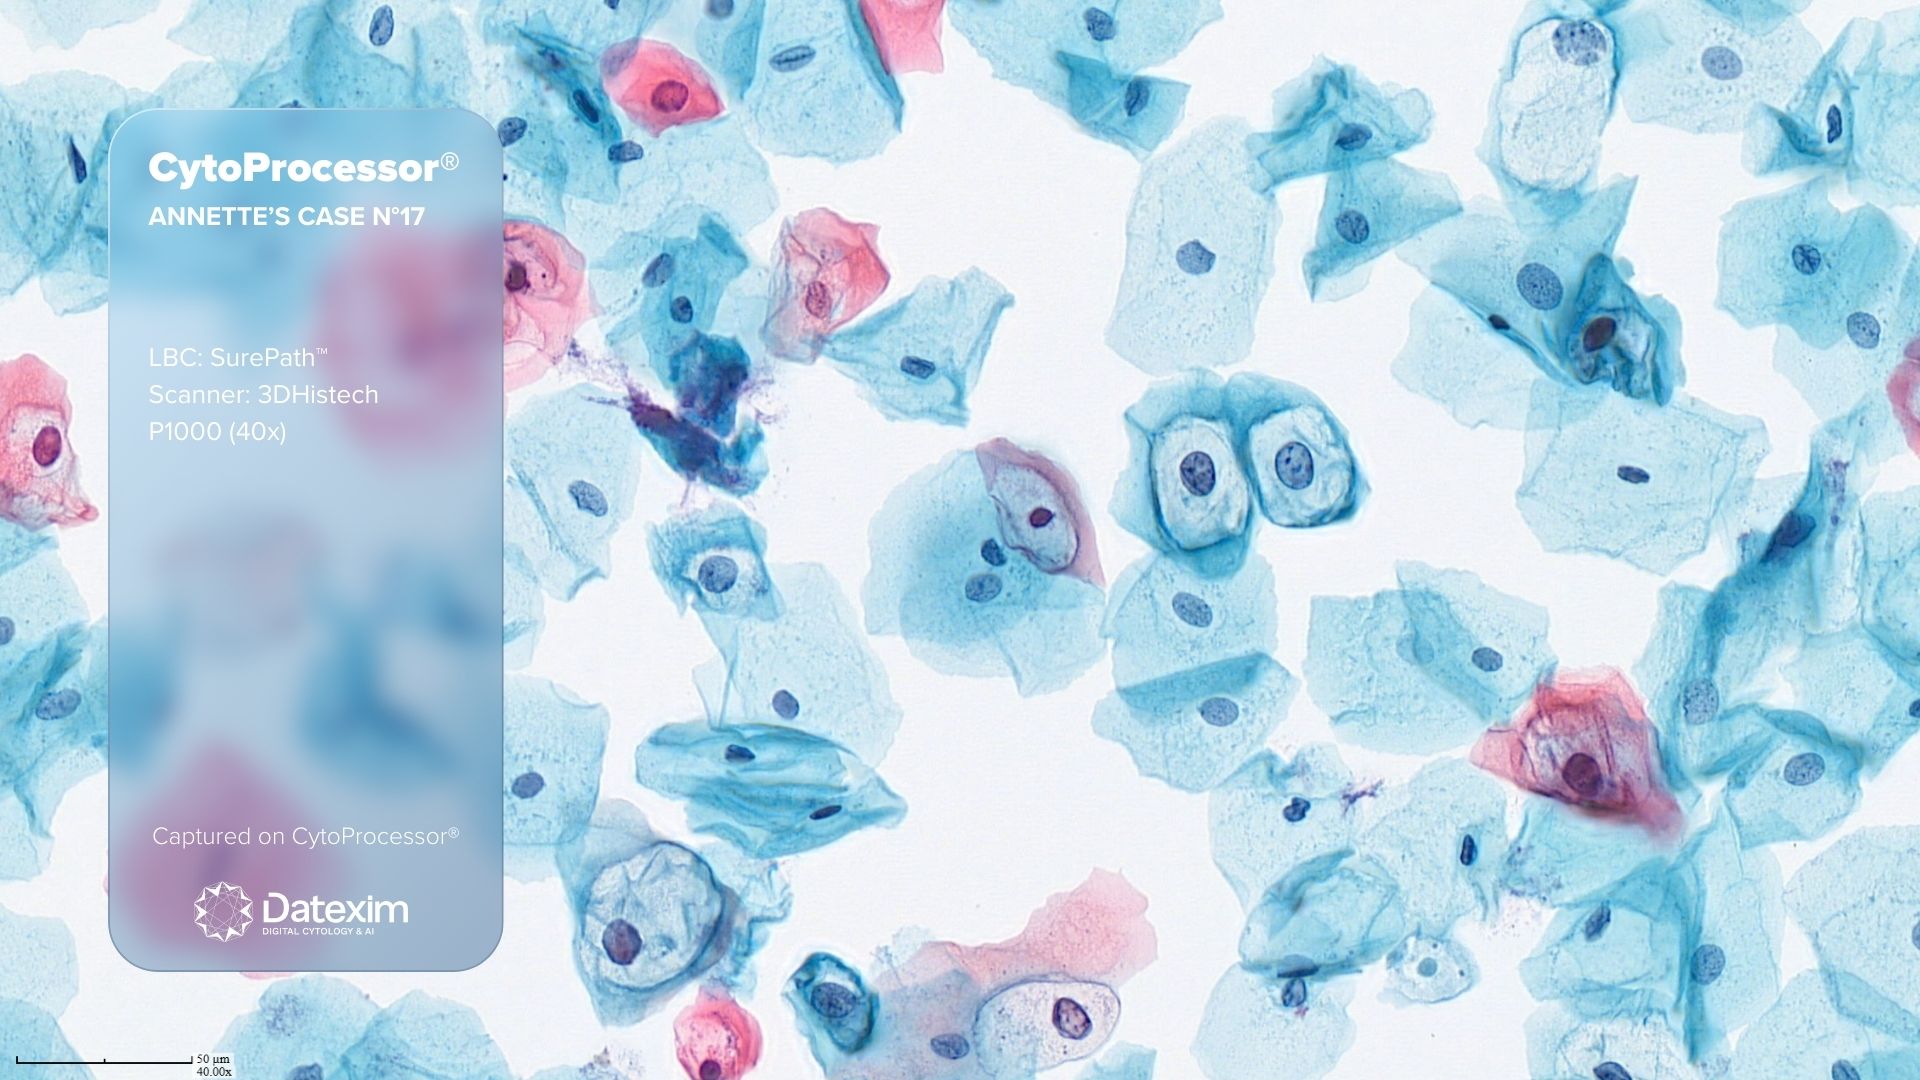

CytoProcessor® - Annette's Case n°17

CytoProcessor® shows the presence of koilocytes, assisting the screener in making an accurate and reliable diagnosis for LSIL.

CytoProcessor® shows the presence of these koilocytes, on a Liquid Based Cytology slide, at a first glance, thereby assisting the screener in making an accurate and reliable diagnosis for LSIL.

Microscopically characteristics of koilocytes

Mature squamous cells with:

Large clear irregular cavity or halo with sharp border

Enlarged, slightly atypical nucleus and almost never in the centre of the halo

Bi- and multi-nucleation is common

BD SurePath | 3DHistech Pannoramic 1000 (40x)